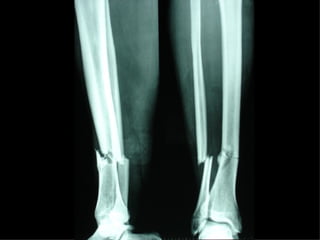

Fratture multiple delle ossa lunghe

Dal Gennaio 2000 al Febbraio 2006 abbiamo trattato 167 fratture chiuse  con placca percutanea  in 164 pazienti :  27 lesioni diafisarie di gamba, 12 piloni tibiali ,  11 fratture prossimali di tibia, 36 fratture sovracondiloidee di femore, 17 fratture diafisarie di femore, 43 fratture metaepifisarie prossimali di omero, 21 diafisarie d’omero.  156 guarigioni 8 fallimenti